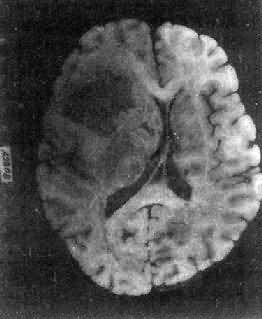

肉眼观,肿瘤为数厘米的结节至巨大块状。分化较好的肿瘤,境界不清;而分化程度较低的肿瘤则境界分明。瘤体灰白色。质地视肿瘤内胶质纤维多少而异,或硬、或软、或呈胶冻状外观,并可形成大小不等的囊腔。由于肿瘤的生长、占位和邻近脑细胞的肿胀,脑的原有结构因受挤压而扭曲变形(图16-23)。

图16-23 星形胶质细胞瘤

左大脑半球肿胀,肿瘤边界不清,部分呈胶冻状